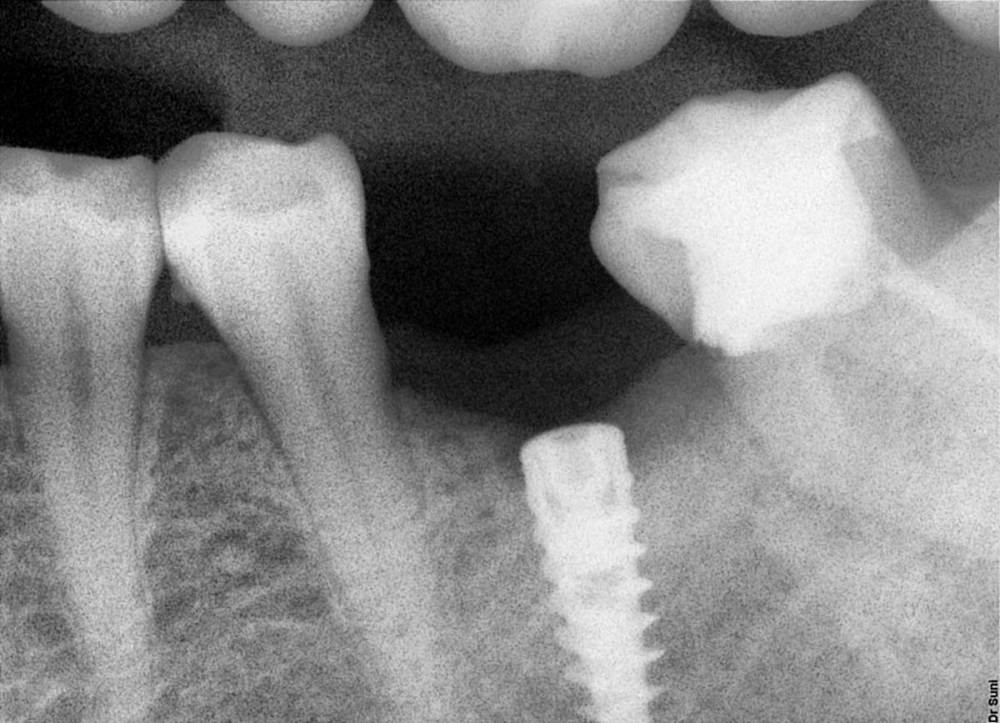

bilal Опубликовано 2 сентября, 2023 Поделиться Опубликовано 2 сентября, 2023 Кто нибудь может подсказать что за имплант? Ссылка на комментарий

Irouil Опубликовано 2 сентября, 2023 Поделиться Опубликовано 2 сентября, 2023 Что-то шестигранное, альфа SPI или любые её копии 1 Ссылка на комментарий

АнтонТЛТ Опубликовано 6 мая, 2025 Поделиться Опубликовано 6 мая, 2025 Лучше прицельный сделать и сфоткать интерфейс шахты имплантата. По оптг больше похож на астру. Ссылка на комментарий

Irouil Опубликовано 7 мая, 2025 Поделиться Опубликовано 7 мая, 2025 21 час назад, АнтонТЛТ сказал: Лучше прицельный сделать и сфоткать интерфейс шахты имплантата. По оптг больше похож на астру. Да, тоже подумал про астру по снимку, но фдм такого там вроде нет Ссылка на комментарий

Irouil Опубликовано 9 мая, 2025 Поделиться Опубликовано 9 мая, 2025 @Doc могу скинуть контакт менеджера, с которой работал я пока жил в Петербурге, может поможет чем-то А тут имплант, на мой взгляд, лучше все равно удалить/заглушить, чем протезировать, но коллега спросил, я лишь пытаюсь помочь) Под OsseoSpeed TX должна подойти протетика от Кореи, но только на лилак (фиолетовую) платформу (осстем регуляр, к примеру) Ссылка на комментарий

Fin Опубликовано 10 мая, 2025 Поделиться Опубликовано 10 мая, 2025 19 часов назад, Irouil сказал: @Doc могу скинуть контакт менеджера, с которой работал я пока жил в Петербурге, может поможет чем-то А тут имплант, на мой взгляд, лучше все равно удалить/заглушить, чем протезировать, но коллега спросил, я лишь пытаюсь помочь) Под OsseoSpeed TX должна подойти протетика от Кореи, но только на лилак (фиолетовую) платформу (осстем регуляр, к примеру) Может на супер тонком абатменте прокатит. Выглядит конечно супер глубоко. Имею подобный опыт руководства. Ссылка на комментарий

Doc Опубликовано 10 мая, 2025 Поделиться Опубликовано 10 мая, 2025 18 часов назад, Fin сказал: Может на супер тонком абатменте прокатит. Выглядит конечно супер глубоко. Имею подобный опыт руководства. Теоретически можно выпутаться из любой ситуации. У Астры есть 20-градусные абатменты высотой 6 мм, они могут помочь. Но только, пардон за мой французский, это насколько же нужно бояться элементарной костной пластики, чтобы зафигачивать имплантат на такую глубину?! Да и кусать такой коронкой уже никогда ничего нельзя будет при таком-то плече! Ссылка на комментарий

Irouil Опубликовано 11 мая, 2025 Поделиться Опубликовано 11 мая, 2025 Тут винт на глаз миллиметров 12 (судя по глубине шахты), от платформы до зенита будет порядка 80% его длины, это слишком много на мой взгляд. Надо, конечно, смотреть в целом что за пациент, но если соматика без криминала, то один из вариантов - удалять, второй - глушить/спилить и пытаться установить другой имплант в обход, в целом можно пробовать даже под ним установить винт длиной в 7 мм, если удастся регенироровать достаточный объем тканей в крестальном отделе, но очень важно исключить инфицирование от импланта/остаточного фрагмента Вариант удаления наверное проще, можно одномоментно крутить в апикальную кортикалку и IDR-подобную аугментацию вокруг, но тут нужно смотреть что там с бугром. 1 Ссылка на комментарий